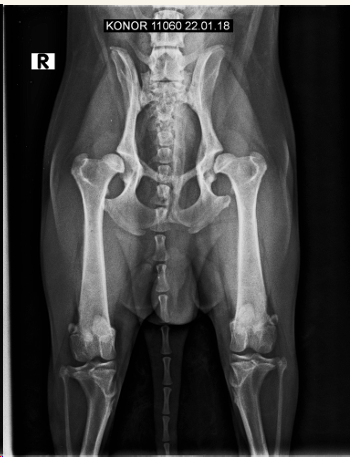

Displasia de cadera:

- Más en perro que en gato

- Pasa de Laxitud articular a subluxación a EDA secundaria

- Incluir la pelvis, femur y rotulas en radiografia.

- Signos radiográficos típicos según el grado ( A---E ) Siendo A un animal sano y E una enfermedad muy avanzada